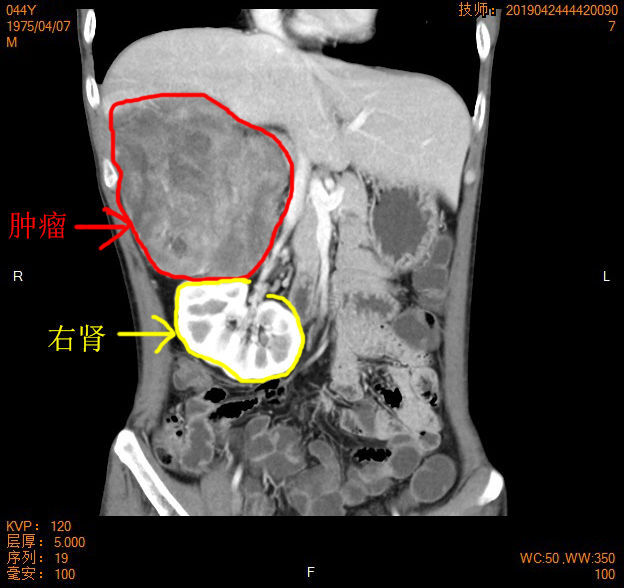

▲术后复查肿物切除干净,右肾回到生理位置

术后,经过短暂的ICU监护和近1个月治疗恢复,林先生能够正常饮食,身体各项指标恢复正常,下肢感觉、运动功能未受到任何影响,出院复查CT显示右肾回到正常生理位置,肿物彻底切除干净,康复出院。出院前,林先生向何裕隆教授团队送来了锦旗,并再三感谢!